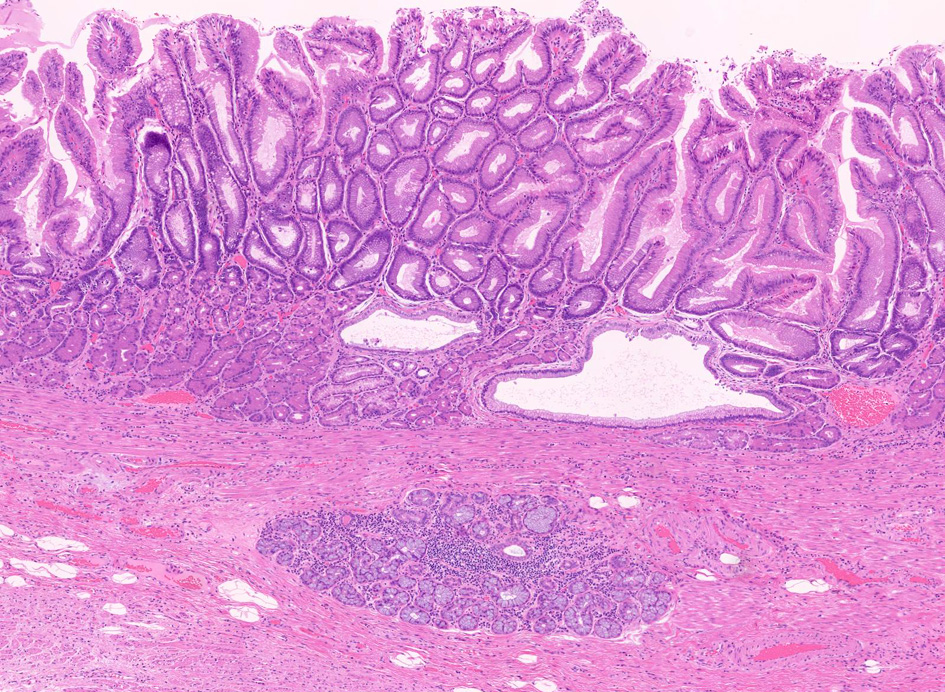

Barrettca02.jpg

Fig.1 Barrett食道 腺癌Fig.2 EGP

固有食道腺(Esophageal Glands Proper:EGP)とは何か

EGPは常に扁平上皮から誘導されてできる腺で, その存在は必ず一度は粘膜内に扁平上皮があったという印であり食道固有の構造である。

扁平上皮島連続切片の観察では,すべての扁平上皮島は固有食道腺と導管を介して結合している

固有食道腺の開口部は必ず扁平上皮で囲まれており, 食道腺の上皮が進展しBarrett上皮ができるとする由来説は誤りである。